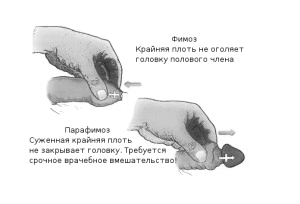

- фимозом,

При набряку і почервоніння голівки, появі хворобливих виразок на ній і крайньої плоті, загальної слабкості та високої температури діагностують гангренозну форму баланопостіта і розвиток фімозу.

- звужується уретра і розвивається фімоз,